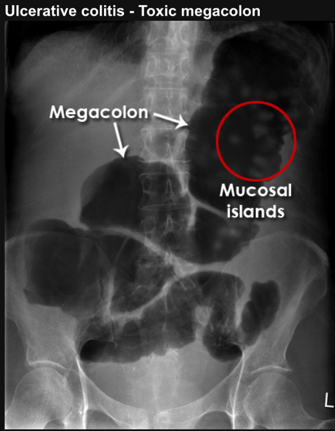

toxic megacolon

persistent inflammation causes loss of muscle tone leading to distension

in toxic megacolon what is seen on AXR

mucosal islands